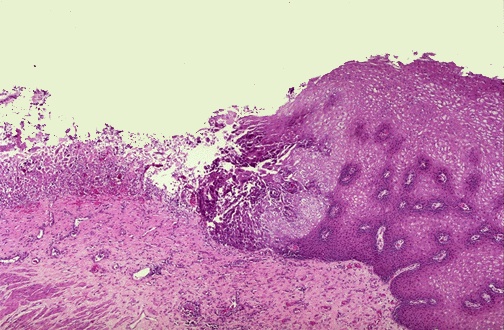

| A herpetic ulcer is seen microscopically to have a sharp margin. The ulcer base at the left shows loss of overlying squamous epithelium with only necrotic debris remaining. In the upper GI endoscopic view below, there are rounded, erythematous ulcerations of the lower esophagus. Biopsies of these lesions reveals intranuclear inclusions in squamous epithelial cells indicative of herpes simplex virus esophagitis. This patient was immune compromised from chemotherapy. |